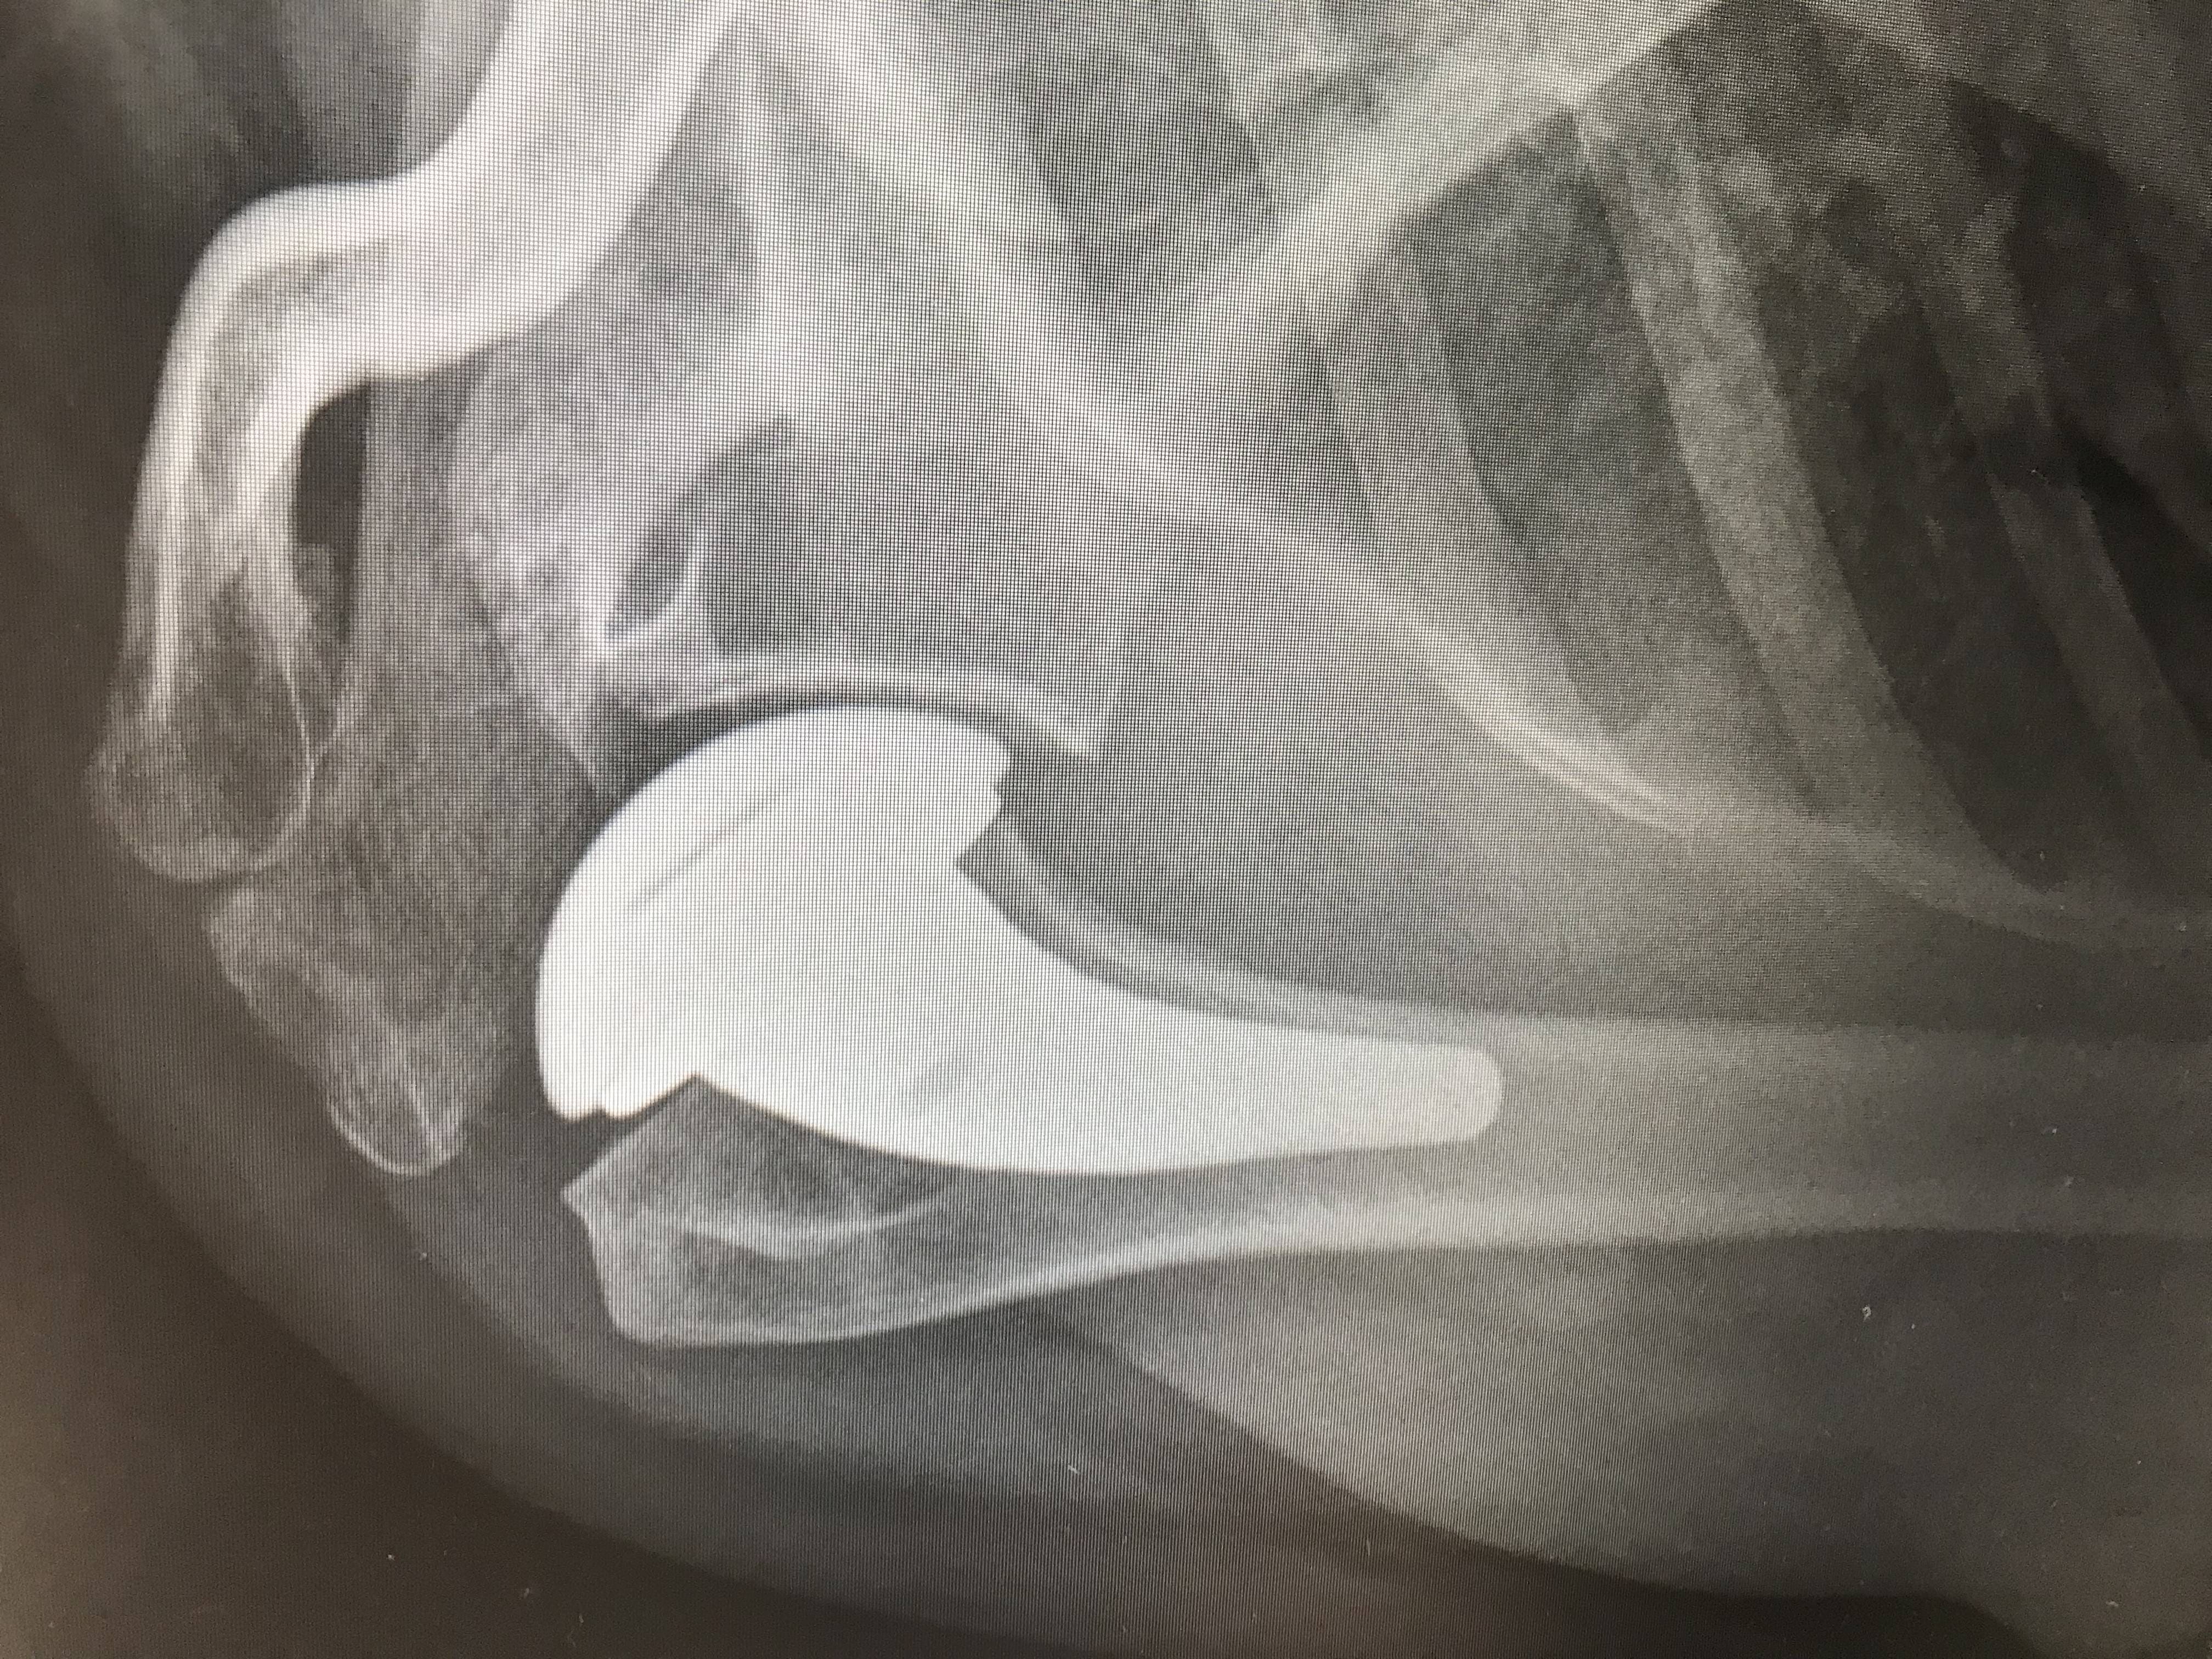

Images of Shoulder Replacement:

X-Ray of Knee Replacement 2